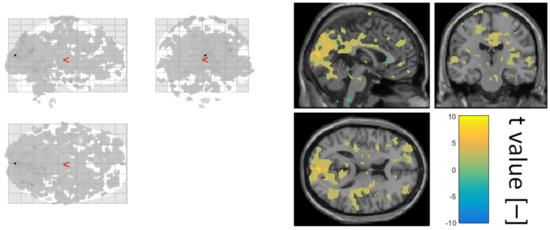

The final step of data quality validation was to define a GLM based on a normalised alpha power time course obtained as the average over all electrodes and check whether the activation lies in the occipital part of the brain. In Figure 5, the second-level statistics over all subjects of an alpha power regressor is visualised.

Figure 5. The visualised second-level statistic t values of a relative alpha power regressor. Shown using xjview at significance level 0.05.